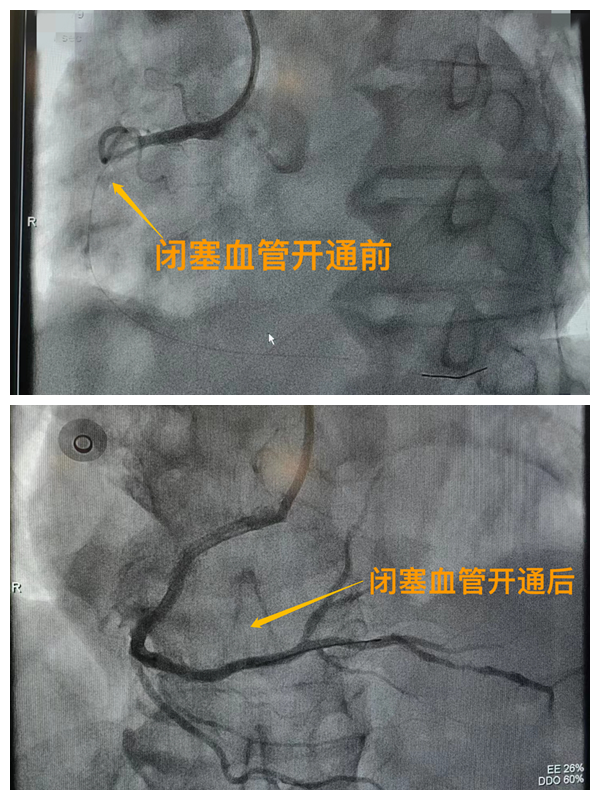

活動開始前,院長王瑾對現(xiàn)場群眾進行了健康科普宣講,她以近期醫(yī)院救治的多例急性心肌梗死患者的癥狀、發(fā)展、急救、手術(shù)、康復全流程情況為例,向小區(qū)群眾講述了心梗的發(fā)病癥狀和院前急救注意事項,以及要及時通過120送至專業(yè)的胸痛中心開展科學、規(guī)范的急救手術(shù)的必要性,講述了心?;颊咿D(zhuǎn)危為安的全過程,得到了廣大群眾的共鳴與好評。

市二院胸痛中心于2021年12月23日通過中國胸痛中心認證,成為國家級胸痛中心,先后開展了冠心病的介入診療、心律失常的心內(nèi)電生理檢查及射頻消融治療、永久起搏器植入、先天性心臟病的介入封堵及臨時起搏器植入、主動脈內(nèi)球囊反搏治療等,完成心臟介入手術(shù)3000余例。多次創(chuàng)造從入院至行急診介入手術(shù)開通血管(入門-導絲通過)30分鐘以內(nèi)記錄,極大保證了患者的生命安全,提高了預后質(zhì)量,挽救了眾多急性心?;颊叩纳?。(尹紅婭       張   靜)